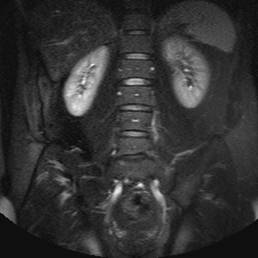

MR af normale nyrer